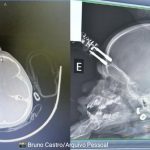

Com apenas 1 ano e 2 meses, derramou acidentalmente água fervente de uma chaleira sobre o corpo, sofrendo queimaduras graves. Foram sete meses de internações, cirurgias e enxertos, período em que os médicos chegaram a duvidar de sua sobrevivência. Contra todos os prognósticos, ele resistiu e cresceu transformando as cicatrizes em símbolos de força.